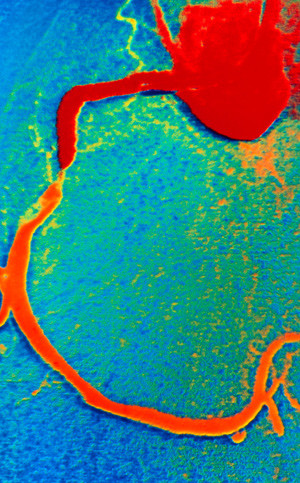

Bruk av sensitive analysemetoder for troponin hos pasienter med akutt koronarsyndrom gir bedre prediksjon av koronare stenoser ved angiografi enn tradisjonelle analysemetoder.

Parallelt med innføringen av sensitive analysemetoder for måling av troponin har retningslinjene for diagnostikk av akutt hjerteinfarkt blitt endret flere ganger de siste årene. Sensitive analysemetoder for troponin skal ha en deteksjonsgrense som er under 99-prosentilen i en referansepopulasjon, med en variasjonskoeffisient under 10 % ved 99-prosentilen. Minst én troponinverdi over 99-prosentilen er en forutsetning for diagnosen. Det er kjent at sensitive troponinanalyser gir viktig prognostisk informasjon hos pasienter med ustabil angina og hjerteinfarkt, men i hvilken grad de bedrer prediksjon av signifikante koronare stenoser hos pasienter henvist til koronar angiografi, har ikke vært kjent.

Ved Kardiologisk avdeling, Oslo universitetssykehus, Rikshospitalet har vi gjennomført en prospektiv studie der vi undersøkte sammenhengen mellom troponinnivåer, NT-proBNP og funn av koronare stenoser med behov for revaskularisering (1). Studien omfattet 458 pasienter henvist til koronar angiografi pga. mistenkt akutt koronarsyndrom. Vi sammenliknet den prediktive verdien av troponin T-nivåer målt ved standard og høysensitiv analysemetode og troponin I-nivåer målt med tre ulike sensitive metoder, samt av NT-proBNP-nivåer. Pasientene ble fulgt i over 3,5 år med tanke på kliniske hendelser.

Studien viser at troponinnivåer målt med sensitive metoder bedrer prediksjonen av behandlingstrengende koronare stenoser hos pasienter med akutt koronarsyndrom, sammenliknet med standardmetoden. Det var minimale forskjeller mellom de sensitive analysemetodene. Jo høyere troponinnivåene var, desto større var risikoen for å ha behandlingstrengende koronare stenoser. For langtidsoverlevelse ga NT-proBNP-målinger bedre prognostisk informasjon enn troponinmålinger. Høye NT-proBNP-nivåer var en uavhengig prediktor for død, selv etter korreksjon for kliniske variabler, kreatininverdi og CRP-nivå.